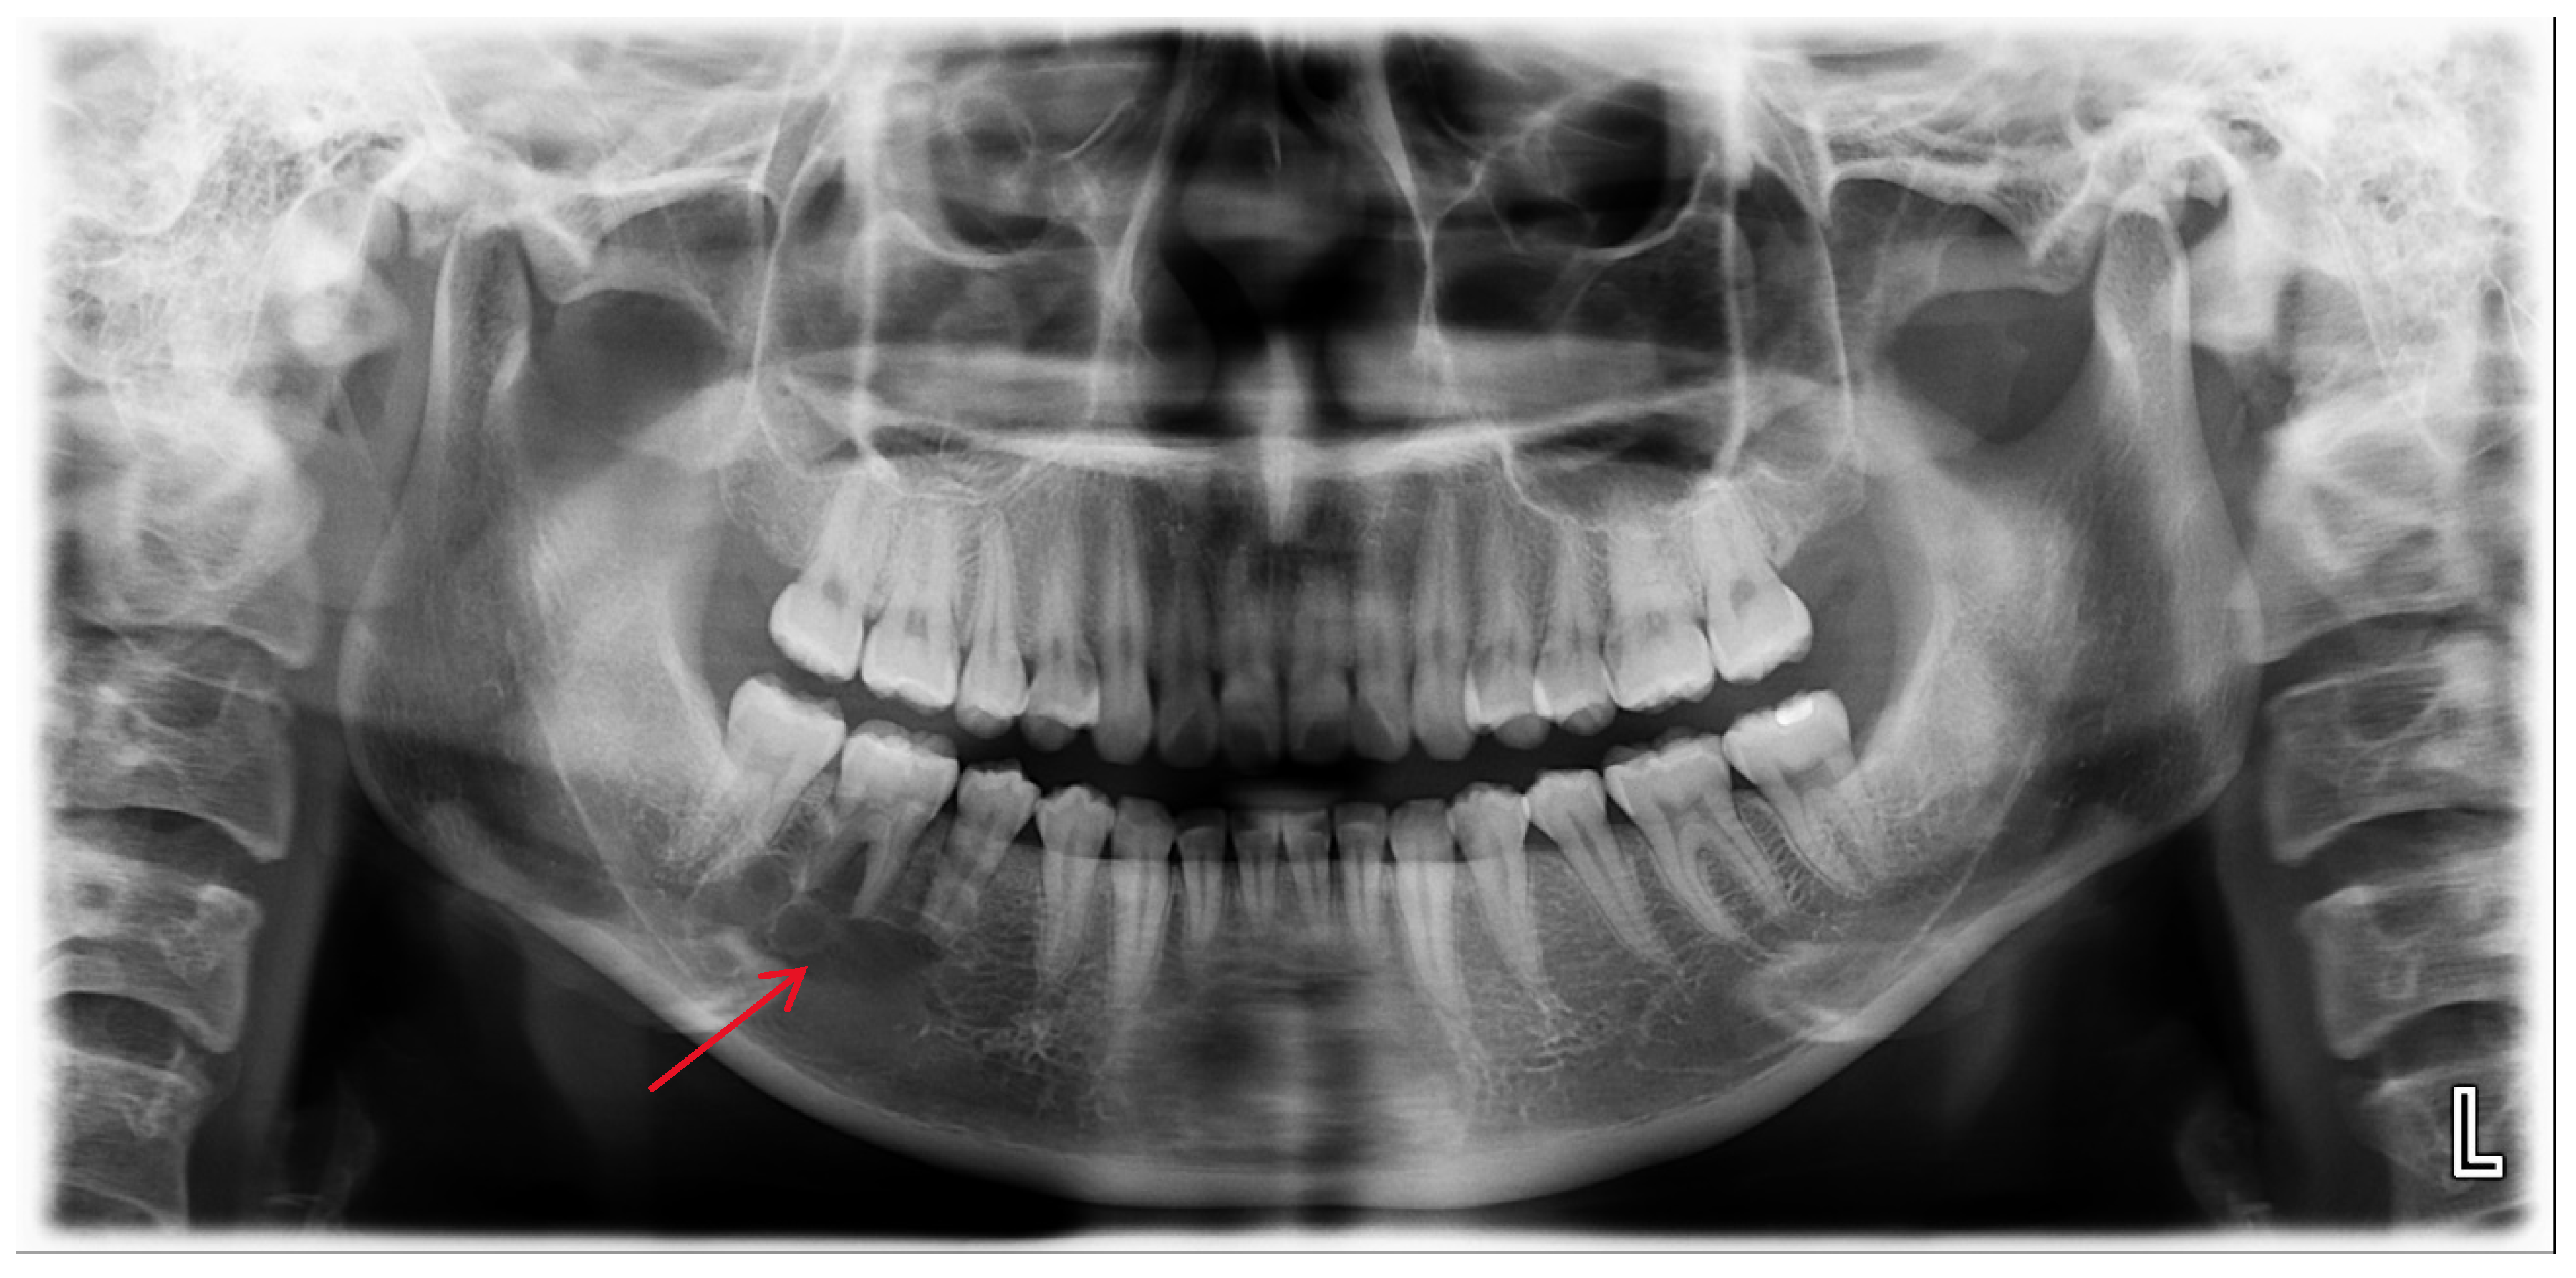

6. Case Presentation

A 25-year-old female was referred to the Department of Oral and Maxillofacial Surgery from a local dental clinic with a primary concern of an intraosseous lesion located below the root apex of the right mandibular first molar. The patient did not report any clinical symptoms. Panorama revealed a multilocular radiolucent lesion with relatively well-defined borders and sclerotic margins in the region of the right mandibular molar. In addition, root resorption was observed in the right mandibular second premolar and first molar (Figure 1). Cone-beam computed tomography (CBCT) revealed thinning of the lingual cortical bone in the areas surrounding the right mandibular second premolar and first molar, as well as inferior displacement of the right mandibular canal (Figure 2). Both the right mandibular second premolar and first molar exhibited slight mobility and percussion sensitivity, while electric pulp testing was positive. Incisional biopsy was the ameloblastoma. To treat the lesion and minimize the risk of recurrence, resection and reconstruction were planned, and virtual surgical planning was performed in collaboration with the SEEANN solution (SEEANN solution, Seoul, Korea). To ensure accurate translation of the VSP to the actual surgery, template models were fabricated for preoperative simulation and intraoperative reference, and surgical guides were designed with multiple registration points for optimal positioning verification during the procedure.

Figure 1.

A multilocular radiolucent lesion with relatively well-defined borders and sclerotic margins in the right mandibular molar region, along with root resorption of the right mandibular second premolar and first molar (red arrow).